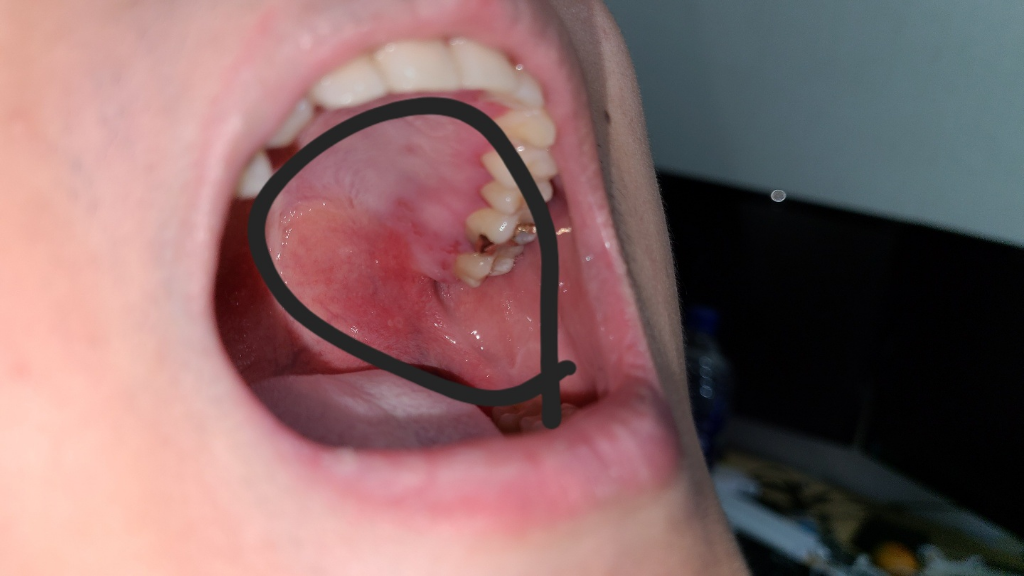

일주일 전에 인후염으로 목에 염증이 가득 나서 병원에서 항생제 처방을 받고 죽이랑 물만 먹고 일주일째 생활중입니다

그런데 목구멍은 점점 괜찮은데 사진처럼 입 안은 헐고 이상한게 나면서 나아지질 않더라고요ㅠㅠ

물만 마셔도 아픕니다 무슨 병이고 해결방법좀 알려주세요ㅠㅠ

입천장으로 구내염이 발생하는 것으로 보이며 구내염은 혀를 포함하여 구강 내벽에 생기는 염증을

의미합니다. 구내염은 흔히 바이러스나 세균, 곰팡균에 의해 발생하며 이 중에서 곰팡이균 칸디다

(Candida albicans)에 의해 발생한 구내염은 칸디다성 구내염 또는 아구창이라고 합니다.

가글과 비타민을 같이 사용하는 것이 좋을 것으로 보이며 항생제로 인해 발생하는 경우도 있어

현재 복용 중인 항생제를 종료하는 것이 좋을 것으로 보입니다.